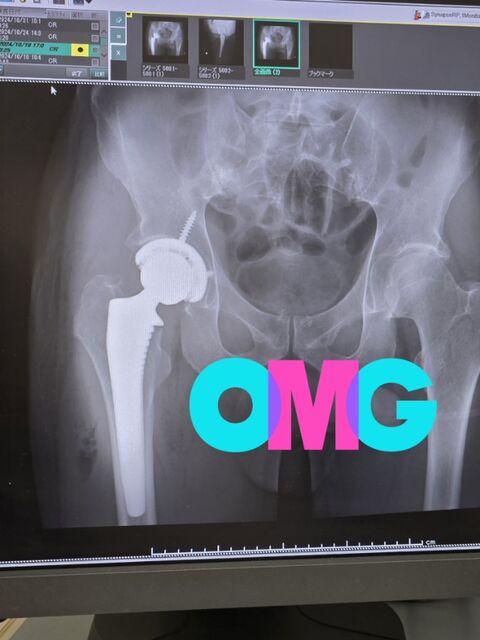

まず、事故のその後ですが10月16日に手術をしてこんな感じ。

私の恥ずかしいシースルー写真(⁎˃艸˂⁎)

骨折したのは大腿骨の骨頭なのですが、それを受ける側の骨にも皿を埋込みネジ補強。